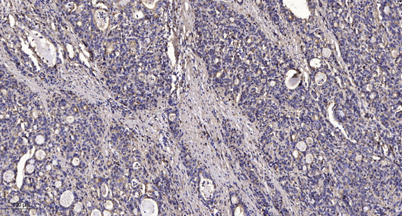

IHC

Recomended Dilution IHC-p 1:50-200, WB 1:500-2000